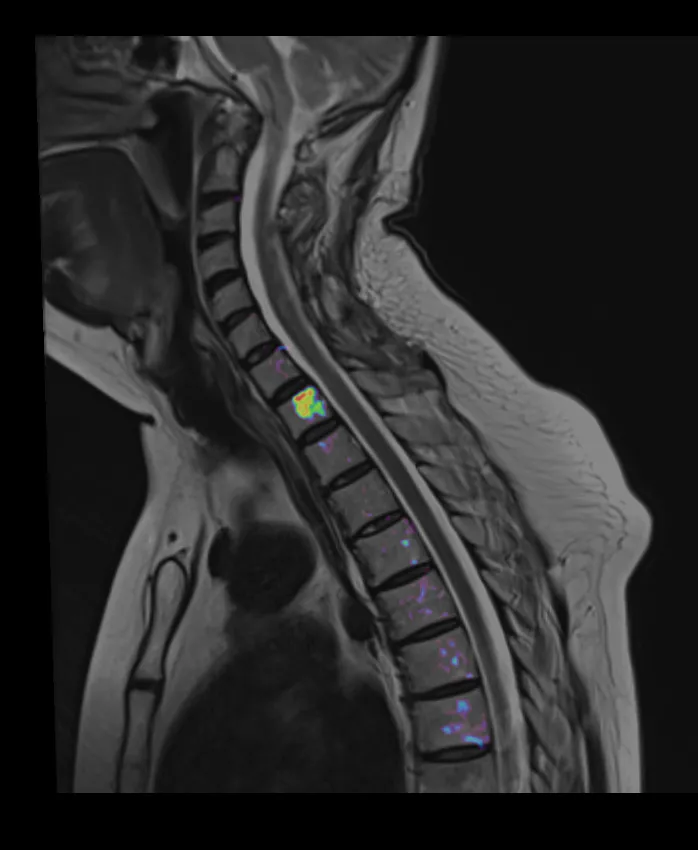

Магнітно-резонансна томографія (МРТ)  Магнітно-резонансна томографія (МРТ)

Чітке зображення МРТ грудної клітки в клініці "Оберіг" у порівнянні зі "звичайним" МРТ

• Технологія "псевдо-ПЕТ" використовується для діагностики метастатичних уражень, лімфоми.